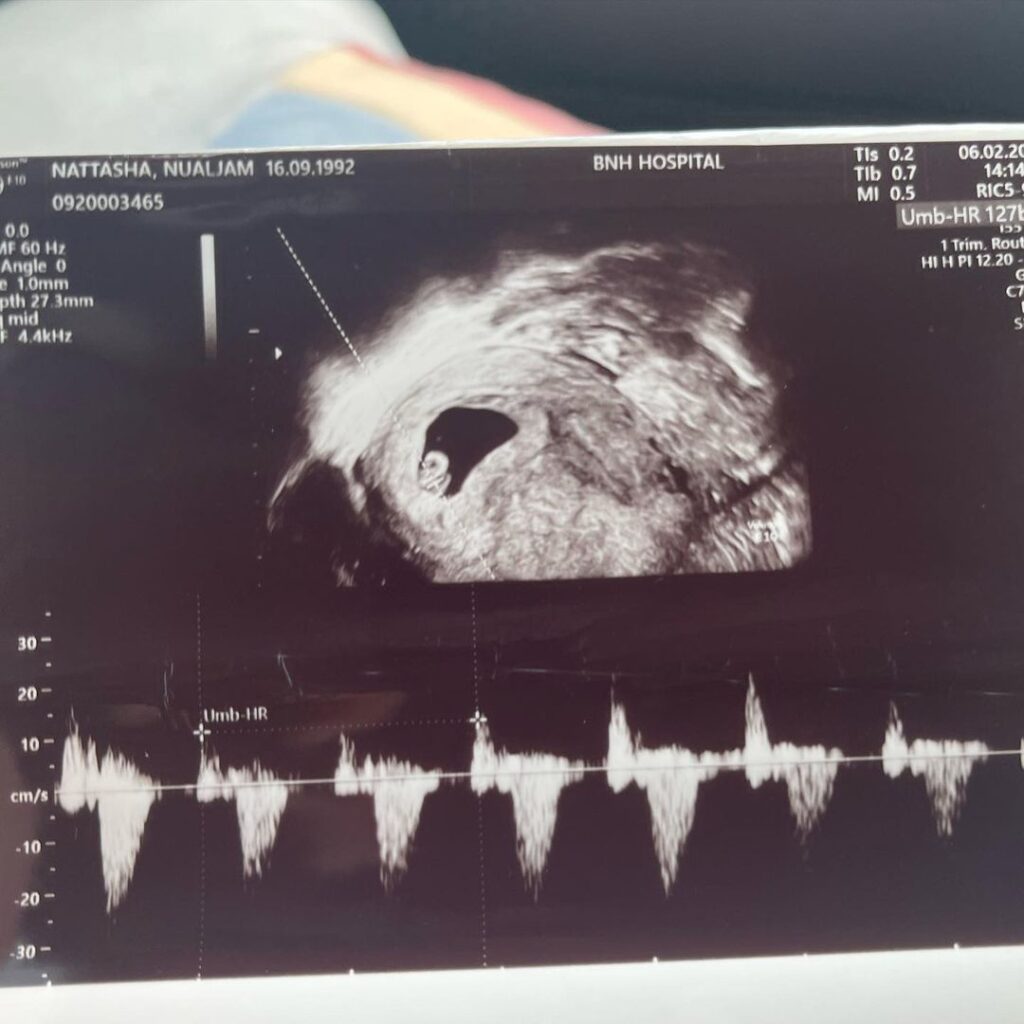

แต่ดูเหมือนว่าท้องนี้ สาว “แนท” จะแพ้ท้องหนัก ทั้งอาเจียน และกินไม่ค่อยได้ จนต้องเข้าแอดมิทที่โรงพยาบาล เพื่อให้น้ำเกลือและเลือด เป็นการบำรุง

โดยสาว “แนท ณัฐชา” ได้โพสต์ภาพขณะที่นอนแอดมิทที่โรงพยาบาล พร้อมกับบอกว่า “เติมพลังก้อนนน หลังจากอาเจียน กินไม่ค่อยได้ จบลงที่ ให้น้ำเกลือ และเลือดจ้า🤣 คิดถึงปะป๊า กะ เรม่า เลย จะรีบกลับไปหาทั้งคู่ คราวนี้กลับไปลูกจะหายแพ้ท้องแน่นอน ในนามพระเยซู อาเมน”